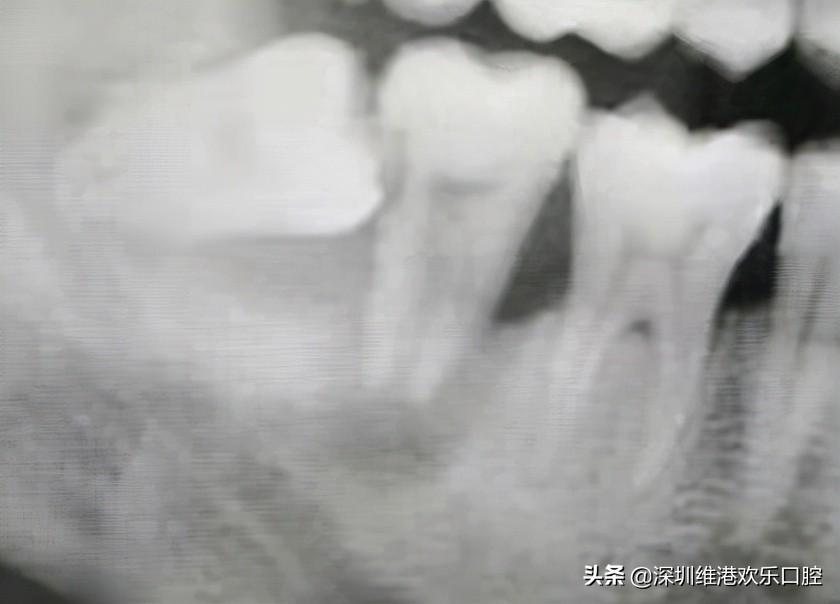

一位患者,智齒長(zhǎng)歪頂壞了鄰牙,導(dǎo)致鄰牙鬆動(dòng),極其容易脫落,患者自己也一度以為可能保不住了。但是高主任在仔細(xì)檢查了患者的實(shí)際情況,認(rèn)為還有保留住的可能。所以高利民主任先把這個(gè)極松的7號(hào)牙和6號(hào)牙用玻璃離子粘結(jié)穩(wěn),先將7牙磨低磨小開髓置Fc棉暫封,然后拔掉智齒,等7牙慢慢恢復(fù)。經(jīng)過(guò)幾個(gè)月后,患者的原始牙得到了很好的恢復(fù)保留。